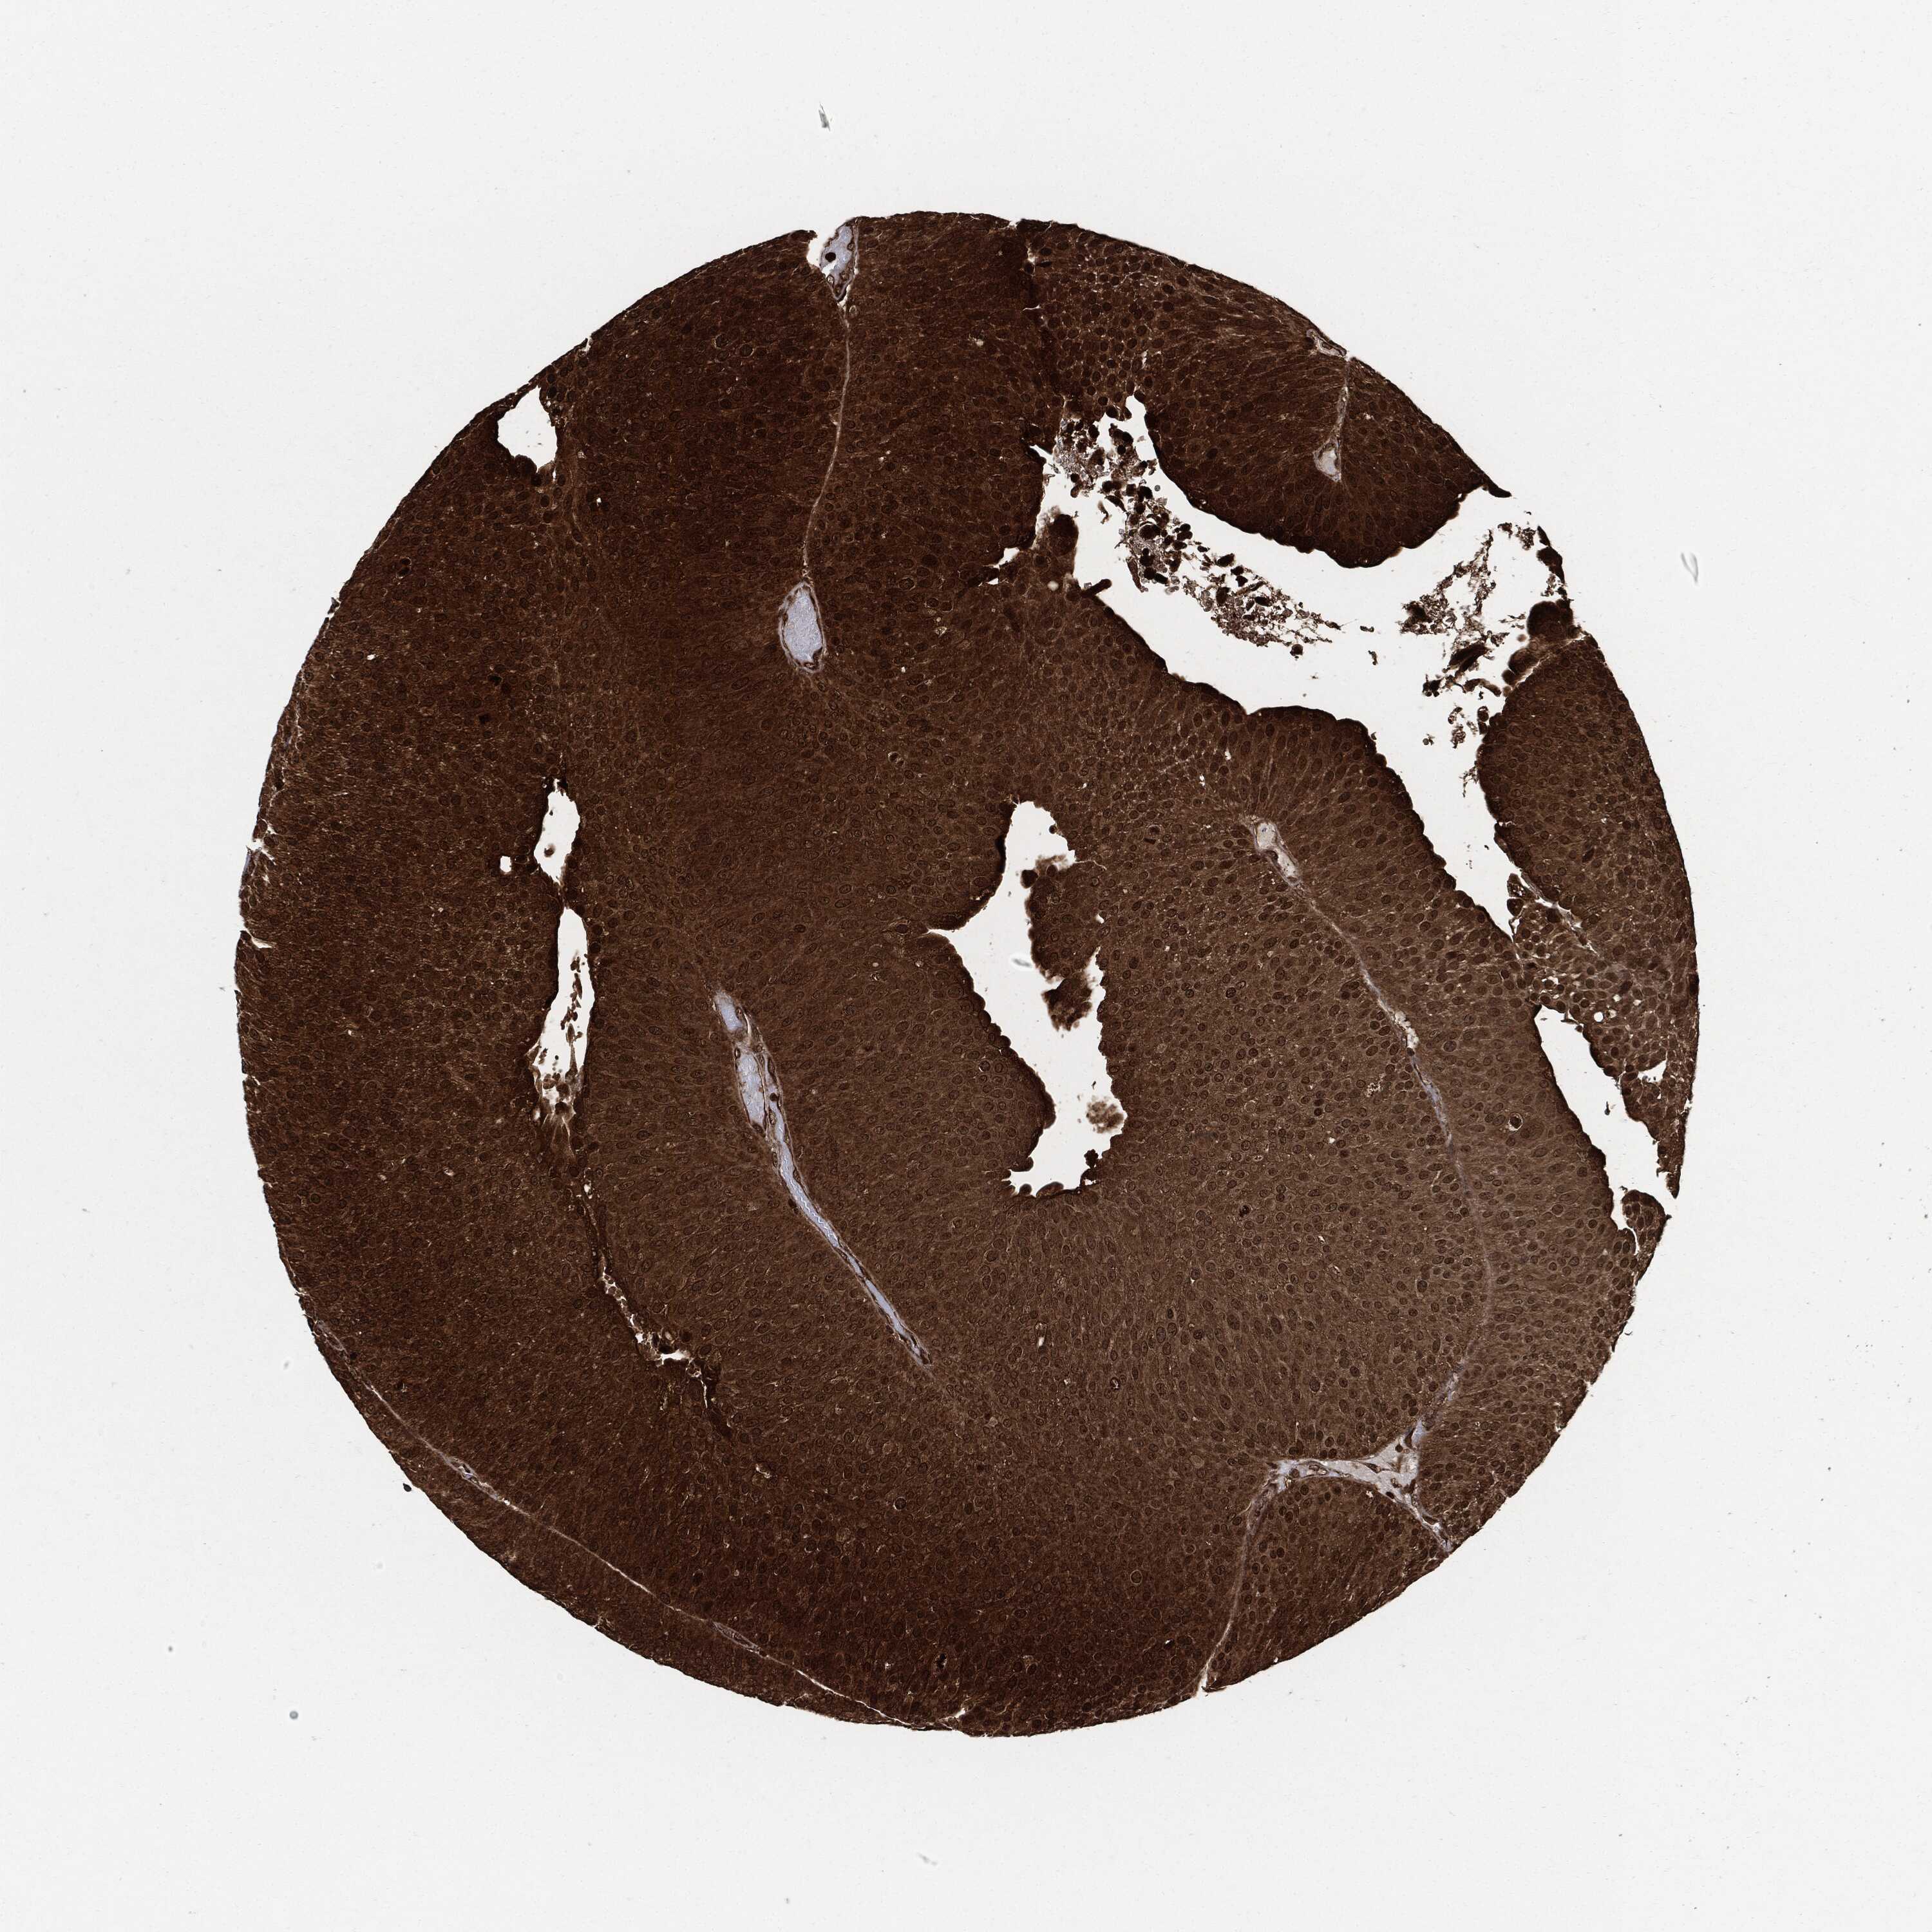

UROTHELIAL CANCER - Protein expressioni

A mouse-over function shows sample information and annotation data. Click on an image to view it in a full screen mode. Samples can be filtered based on level of antibody staining by selecting one or several of the following categories: high, medium, low and not detected. The assay and annotation is described here.

Note that samples used for immunohistochemistry by the Human Protein Atlas do not correspond to samples in the TCGA dataset.

Antibody stainingi

Antibody staining in the annotated cell types in the current human tissue is reported as not detected, low, medium, or high, based on conventional immunohistochemistry profiling in selected tissues. This score is based on the combination of the staining intensity and fraction of stained cells.

Each image is clickable and will lead to virtual microscopy that enables deeper exploration of all samples and also displays staining intensity scores, fraction scores and subcellular localization as well as patient and tissue information for each sample.

Antibody HPA007925

Antibody HPA011212

Antibody CAB003759

Antibody CAB080290

Urothelial carcinoma, Low grade

Urothelial carcinoma, High grade